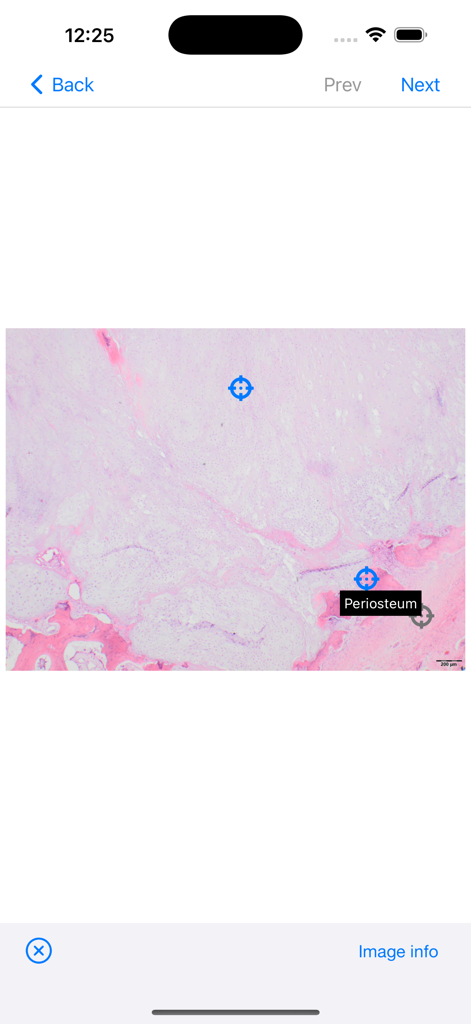

BoSTT - High resolution pathology slide with a labeled periosteum marker in the BoSTT app

High resolution pathology slide with a labeled periosteum marker in the BoSTT app